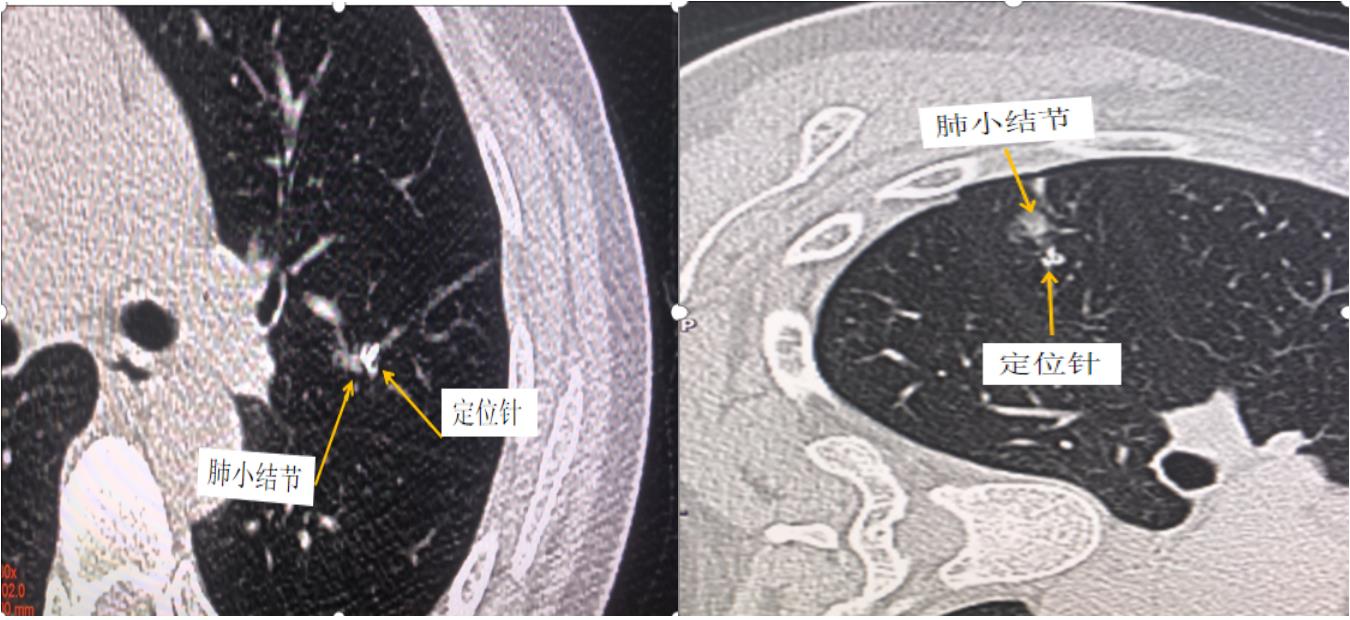

2、CT引導下肺結節(jié)術前定位:對于直徑較小,或距離胸膜邊緣較遠,尤其是磨玻璃結節(jié),術中難以通過手指觸摸定位,需要在術前對此類結節(jié)進行定位。

圖2 術前輔助胸外科CT引導下穿刺肺小結節(jié)定位